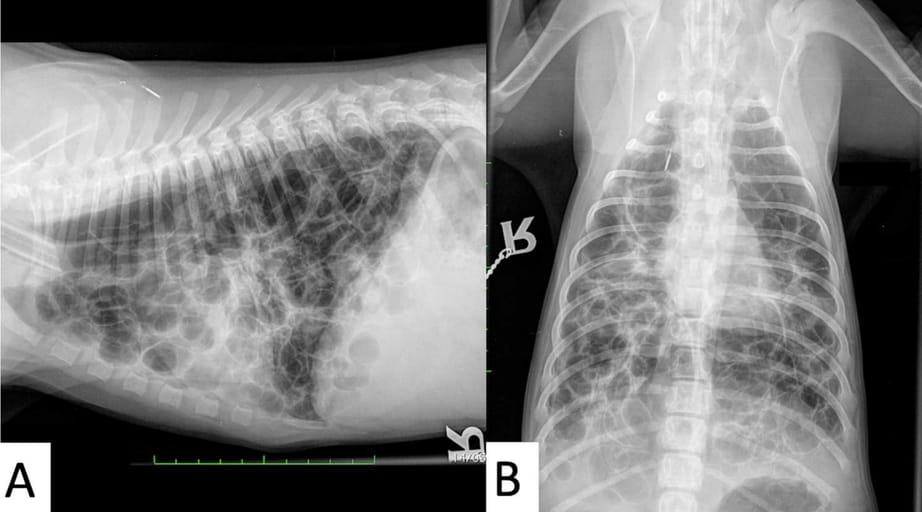

Figure 1 Right lateral (A) and dorsoventral (B) radiographs of the thorax. There are multifocal thin- walled and gas- illed rounded cystic lesions

throughout the lung ield, measuring up to 30 mm in diameter. There is no normal lung pattern identiied. Note the barrel chest, lattening of the

diaphragmatic contours and horizontalisation of the ribs, indicating hyperinlation

Radiographs and CT revealed multifocal, thin-walled, gas-filled cystic lesions throughout all lung lobes, suggestive of pulmonary bullae or cystic bronchiectasis. Signs of pulmonary hyperinflation included a barrel-shaped chest, flattened diaphragm, and horizontal rib orientation. CT confirmed extensive bilateral lesions, ground-glass opacities, and mild pneumothorax. Gross pathology demonstrated subpleural and intraparenchymal bullae. Histologically, dilated bronchi with hypoplastic or absent cartilage, type I and II pneumocytes lining cystic lesions, and variable inflammation were observed. No normal lung parenchyma was preserved.